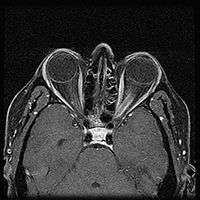

When ONSM is suspected, MRI of the brain or orbits should be performed. This will usually show characteristic findings and confirm the diagnosis.[4]